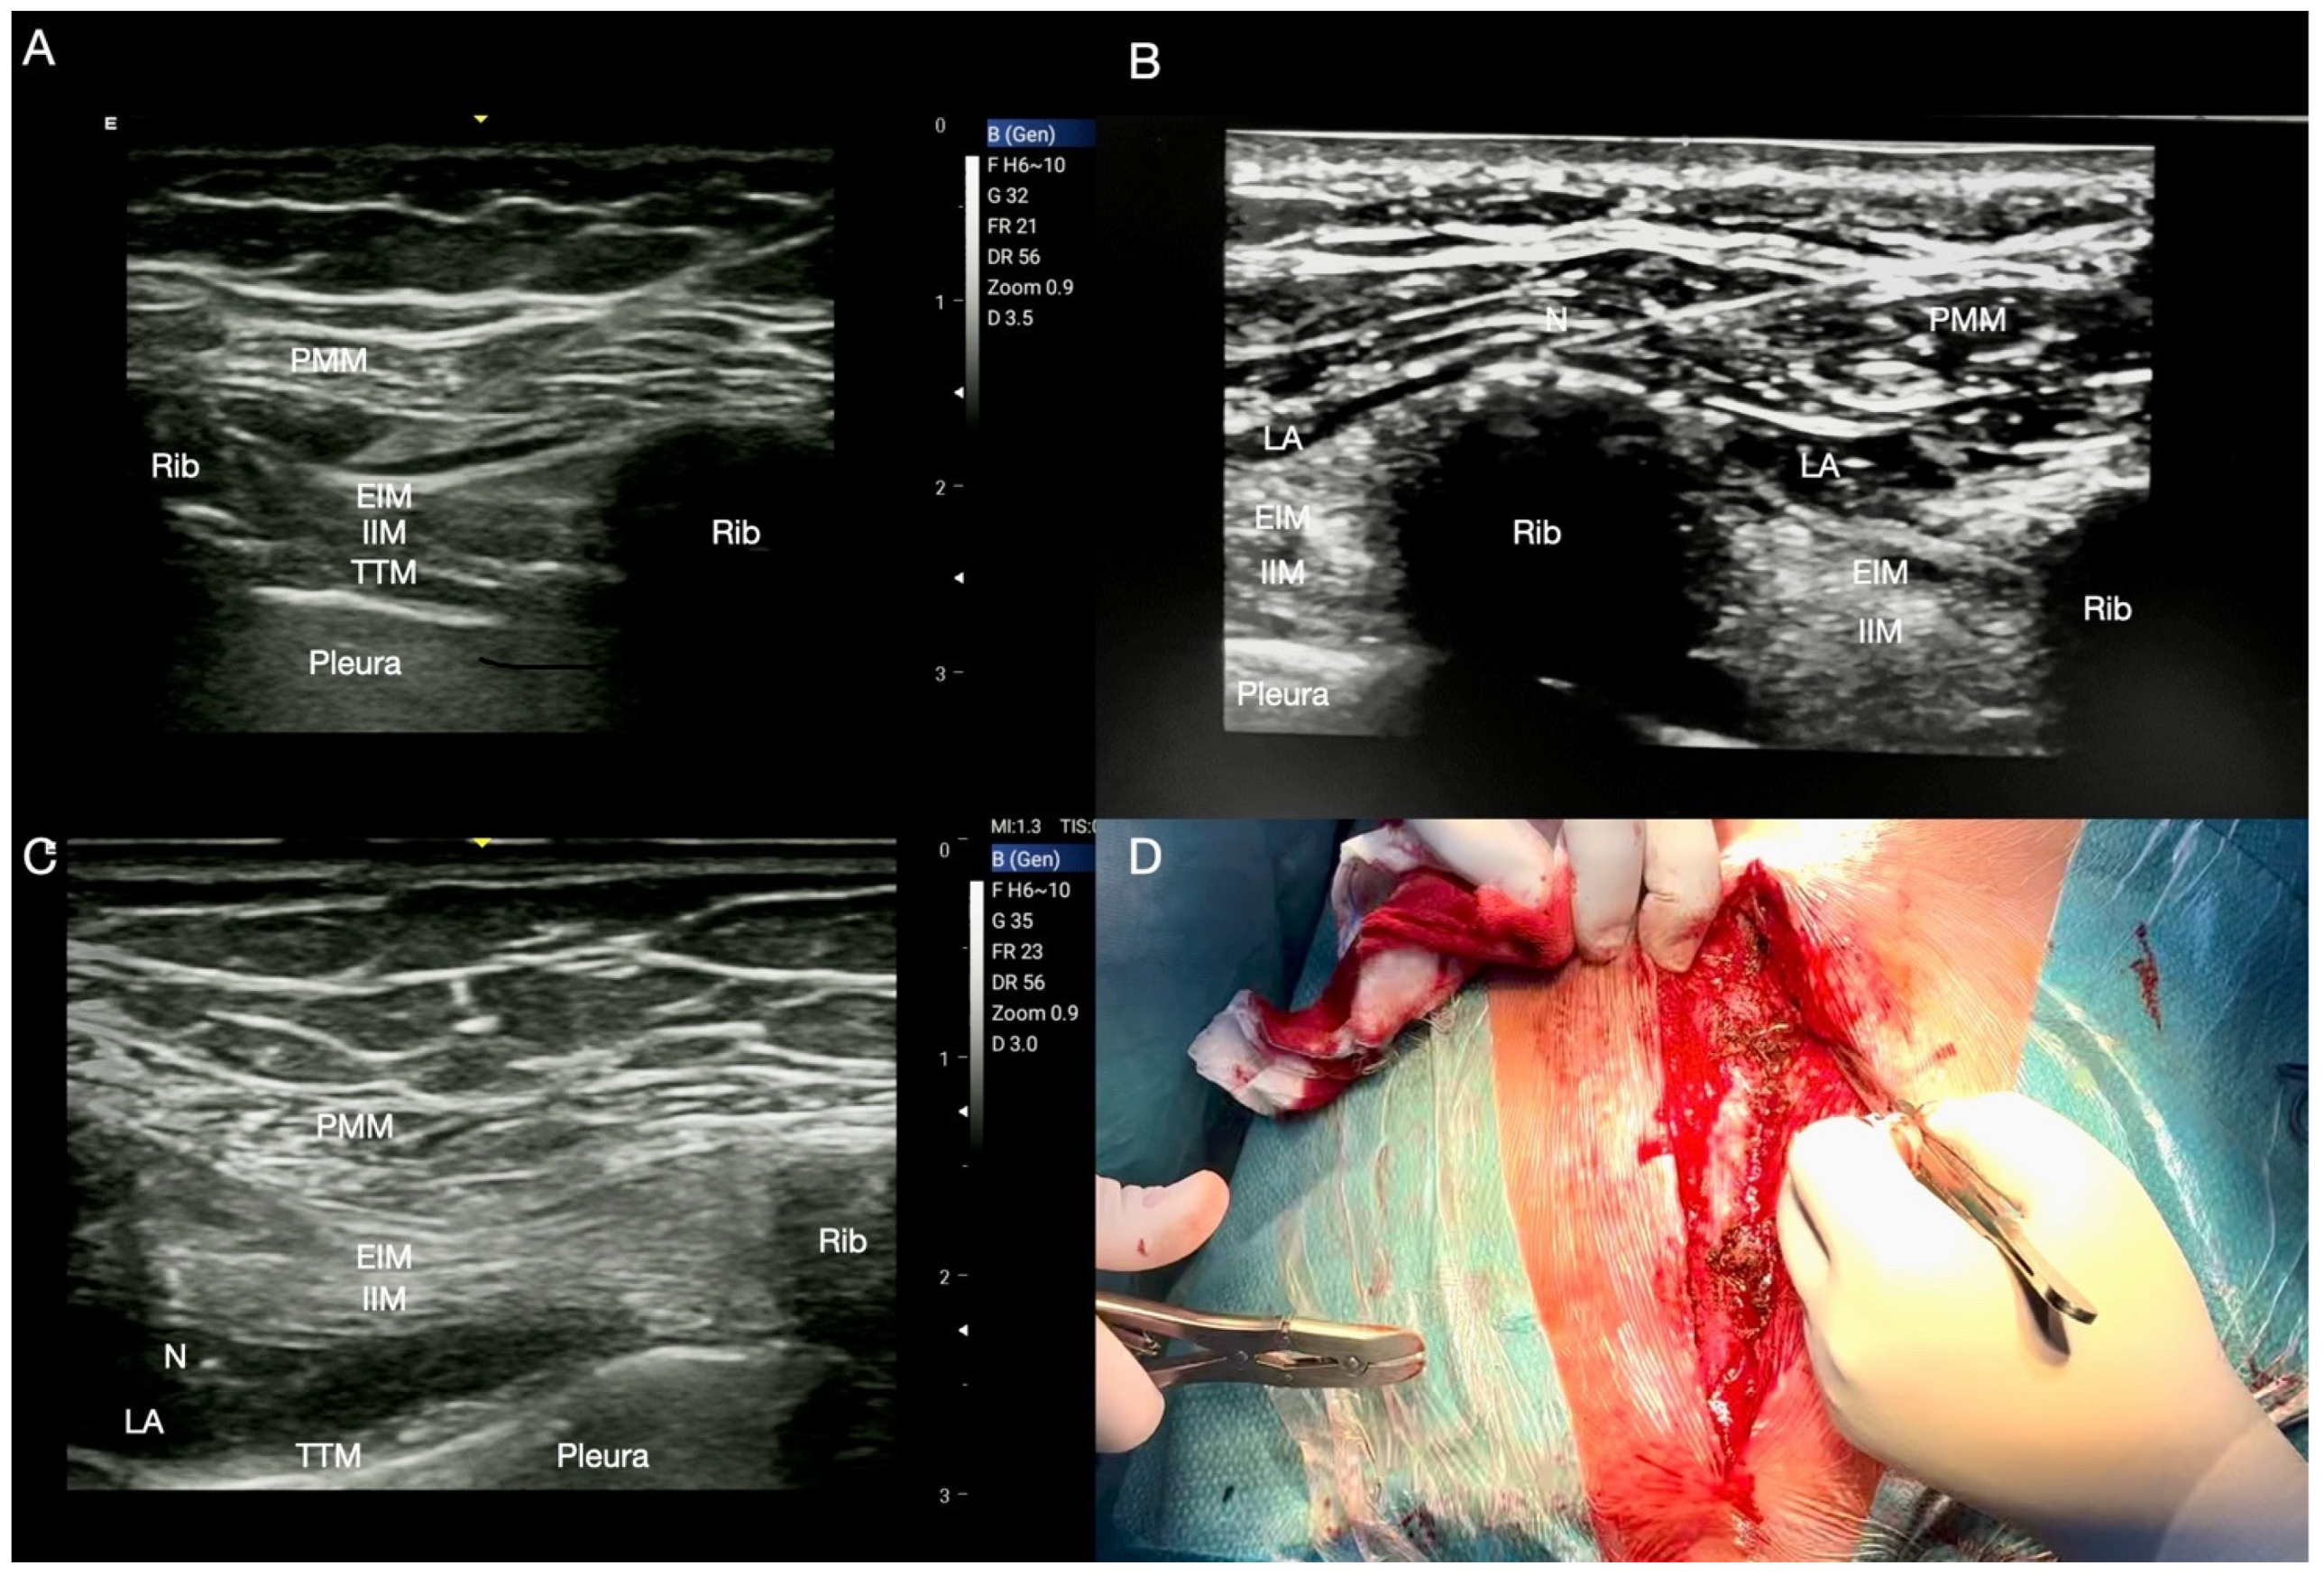

2.1. Pecto-Intercostal Plane (PIP) Block

2.1.1. Technique for Superficial PIP Block

2.1.2. Technique for Deep PIP Block

| PIP | Median sternotomy, mammary region pain after harvesting, sternal resynthesis/fractures, wire removal, sternal wound debridement, muscle flap reconstruction, ICD or pacemaker implant (with addition of SAP). | Anterior cutaneous branches of T2–T6 intercostal nerves. Medial Thoracic region. 2nd and 4th intercostal space. Bilaterally if sternotomy. 5–10 mL of LA. | Placing the tip of the needle on the dome of the rib allows an easier and more homogeneous diffusion of the LA, obtaining a wider dermatomal coverage. |